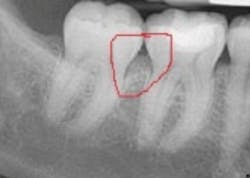

Recently, I was consulting in an office, and the insurance coordinator brought to me a situation almost identical to the one you have described. The hygienist had identified early periodontitis around some posterior teeth with 5 mm pocketing and bleeding. The patient's benefit carrier had denied coverage, stating insufficient bone loss. When I looked at the radiographs, I noticed the loss of bone definition in the molar areas, which is indicative of early periodontitis. There were not blatant vertical defects, yet the bone loss was evident. The X-ray is shown below.

Benefit providers hire people to review claims. Sometimes the reviewers are dentists that work either full or part-time reviewing claims or pre-authorizations. If the reviewer has a large caseload, claims may not get a thorough review or even a close scrutiny of documentation. In the aforementioned case, the bone loss does not appear as a clear vertical defect, but rather as a "fuzzy" area in the interproximal space. In the early stages of periodontitis, early bone loss will show up as loss of bone definition (such as loss of lamina dura).